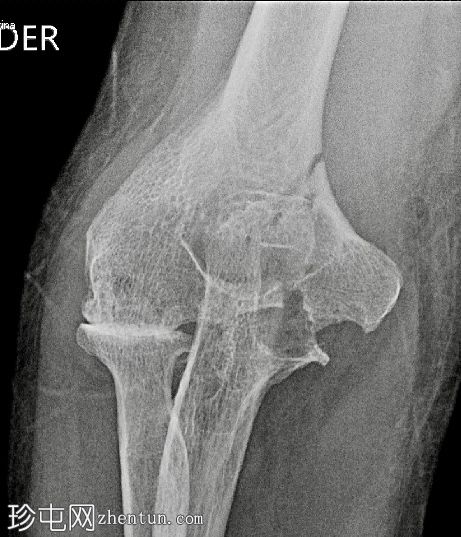

肘部骨折 - 背景为血友病性关节病

正位片

正位片(边缘增强)

肘关节骨折,AO/OTA B2型。

大面积骨侵蚀。

关节间隙狭窄。

血友病是一种疾病,患者由于反复关节积血和随之而来的关节活动减少,导致骨质疏松,从而易发生骨折和骨侵蚀。许多患者由于医护人员担心出血并发症而未接受适当的治疗。本病例旨在展示一个成功的手术过程及其良好的预后。